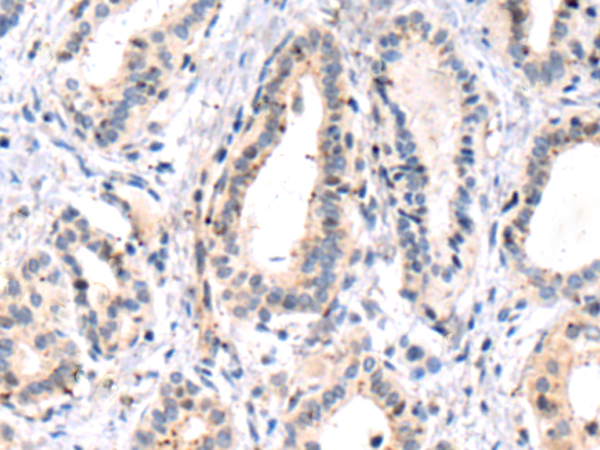

分类: 科研抗体货号: P10599别名:应用: WB,IHC反应种属: Human, Mouse, Rat